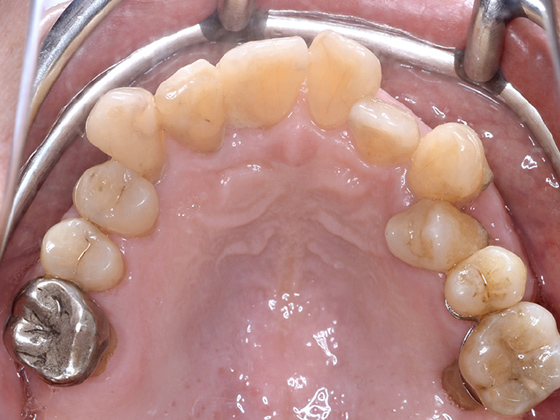

治療前

この症例では下顎の歯周病が特に進行していて、歯がクラグラで噛みにくい為、下の歯を抜歯してオールオン4で治療、上は特に歯周病が進行している左側の大臼歯を抜歯して経過観察することにしました。